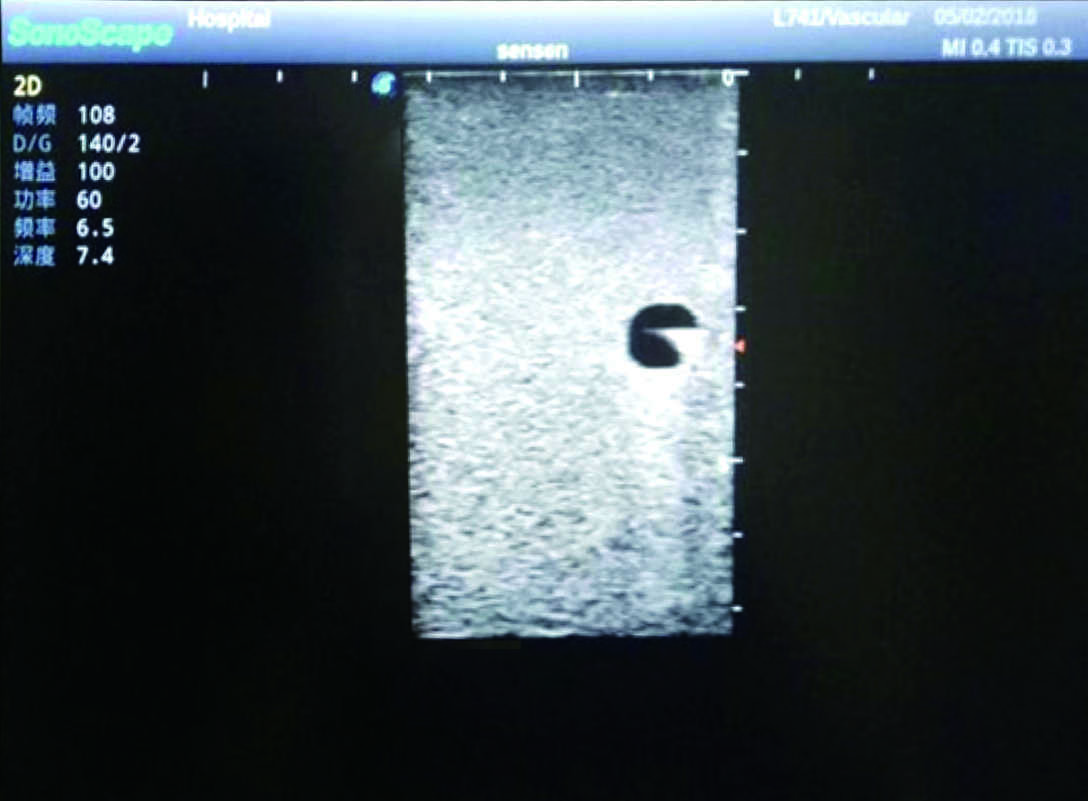

2)   It can be used by real ultrasound machines

3)   Clear and real images of the tissues and organs (basilic vein and superior vena cava)

5)   Observe the guide wire marches

6)   Detect whether the catheter is properly placed